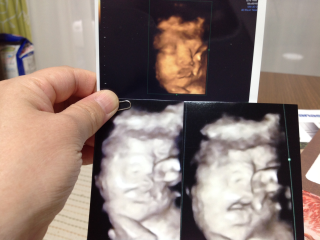

前回30Wの健診エコーでブチャイクに写った我が娘。今回はエコープラスコンデジで動画撮影。かわいく写って一安心(ToT) ただ…BPD8.6(35W相当)AC27.5(33W相当)FLは31W相当と、頭と胴体はデカく足は短いというタラちゃんのような体型にお育ちになっているようだ…できれば足が長くなってほしいワガママ親心。 推定体重は1964gでした。 母体体重は妊娠前+2.9kgでいい感じだけど足の浮腫みと今回初めて尿蛋白が出てしまった。対策は大概やり尽くしているからこれで悪化して管理入院になったらどうしようとまた別な心配事ができてしまった。